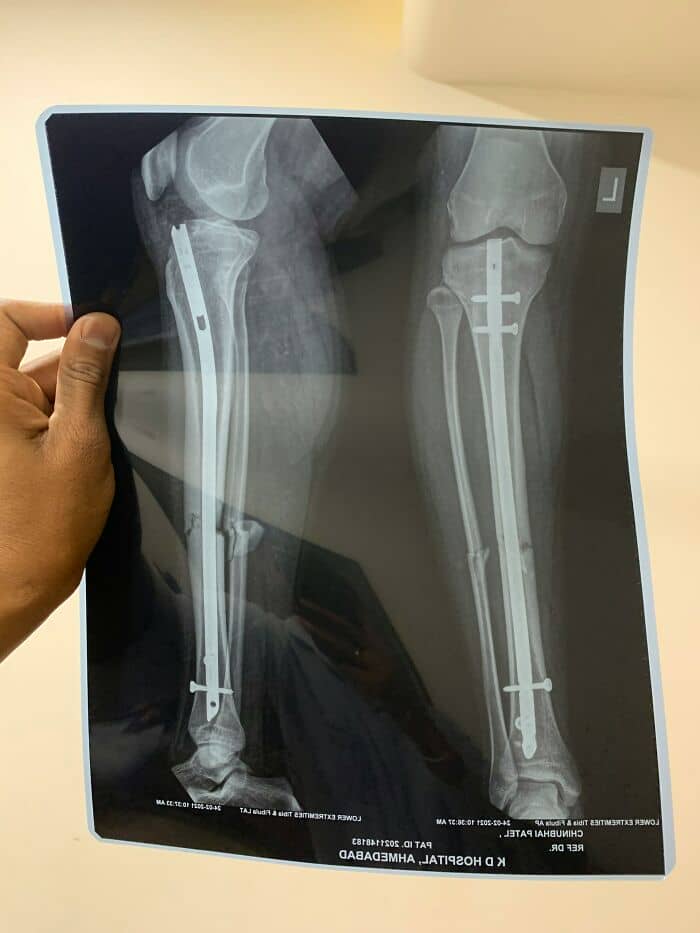

I work as a statistician in a major hospital so I see and catalogue A LOT of weird things.

Worst thing id seen was someone come in complaining of leg pain and showing signs of septic shock. After examination dr orders scans and theres 2 metal rods (one in each leg) that weren’t on their file. Turns out the patient has been to SE Asia to get a height altering surgery and the ‘dr’ had used items youd pick up from the local hardware store to fix the bones after breaking.

After extensive surgery patient lost the lower part of one leg and was lucky to keep the 2nd.